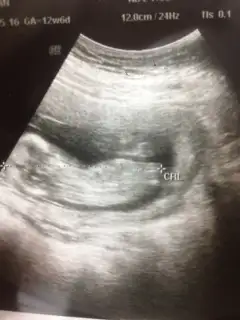

PrenssCvp için teşekkürler . Bide bu son fıtosu var ikiside çok farklı sznkiEki Görüntüle 1363266

On haftalık demişsin çok erken. Bu hafta kız erkek pek fark olmazki güzelim. Erkek geçti ama içimden erkege benzettim yani. Gönlüne göre olsun inşallahLütfen bi bakın çok merak ediyorum

Ben zaten çok anlamam tatlım Allah gönlüne göre versin inşallah. Ben de 18 haftada öğrenmiştim iki hafta daha merak et bakalim sonra net öğrenirsin. Beklemesi merak etmesi bile çok güzellSağol Cnm inş.. Radyoloji uzmanim bakmıştı bu ggörüntüler onun baktıkları içindendi kız demişti... Devletteki doğum dr u erkeğe benzetti bakalım inş iki haftaya belli olur o zaman randevum baya geç öğrenmiş olucam

On haftalık demişsin çok erken. Bu hafta kız erkek pek fark olmazki güzelim. Erkek geçti ama içimden erkege benzettim yani. Gönlüne göre olsun inşallah